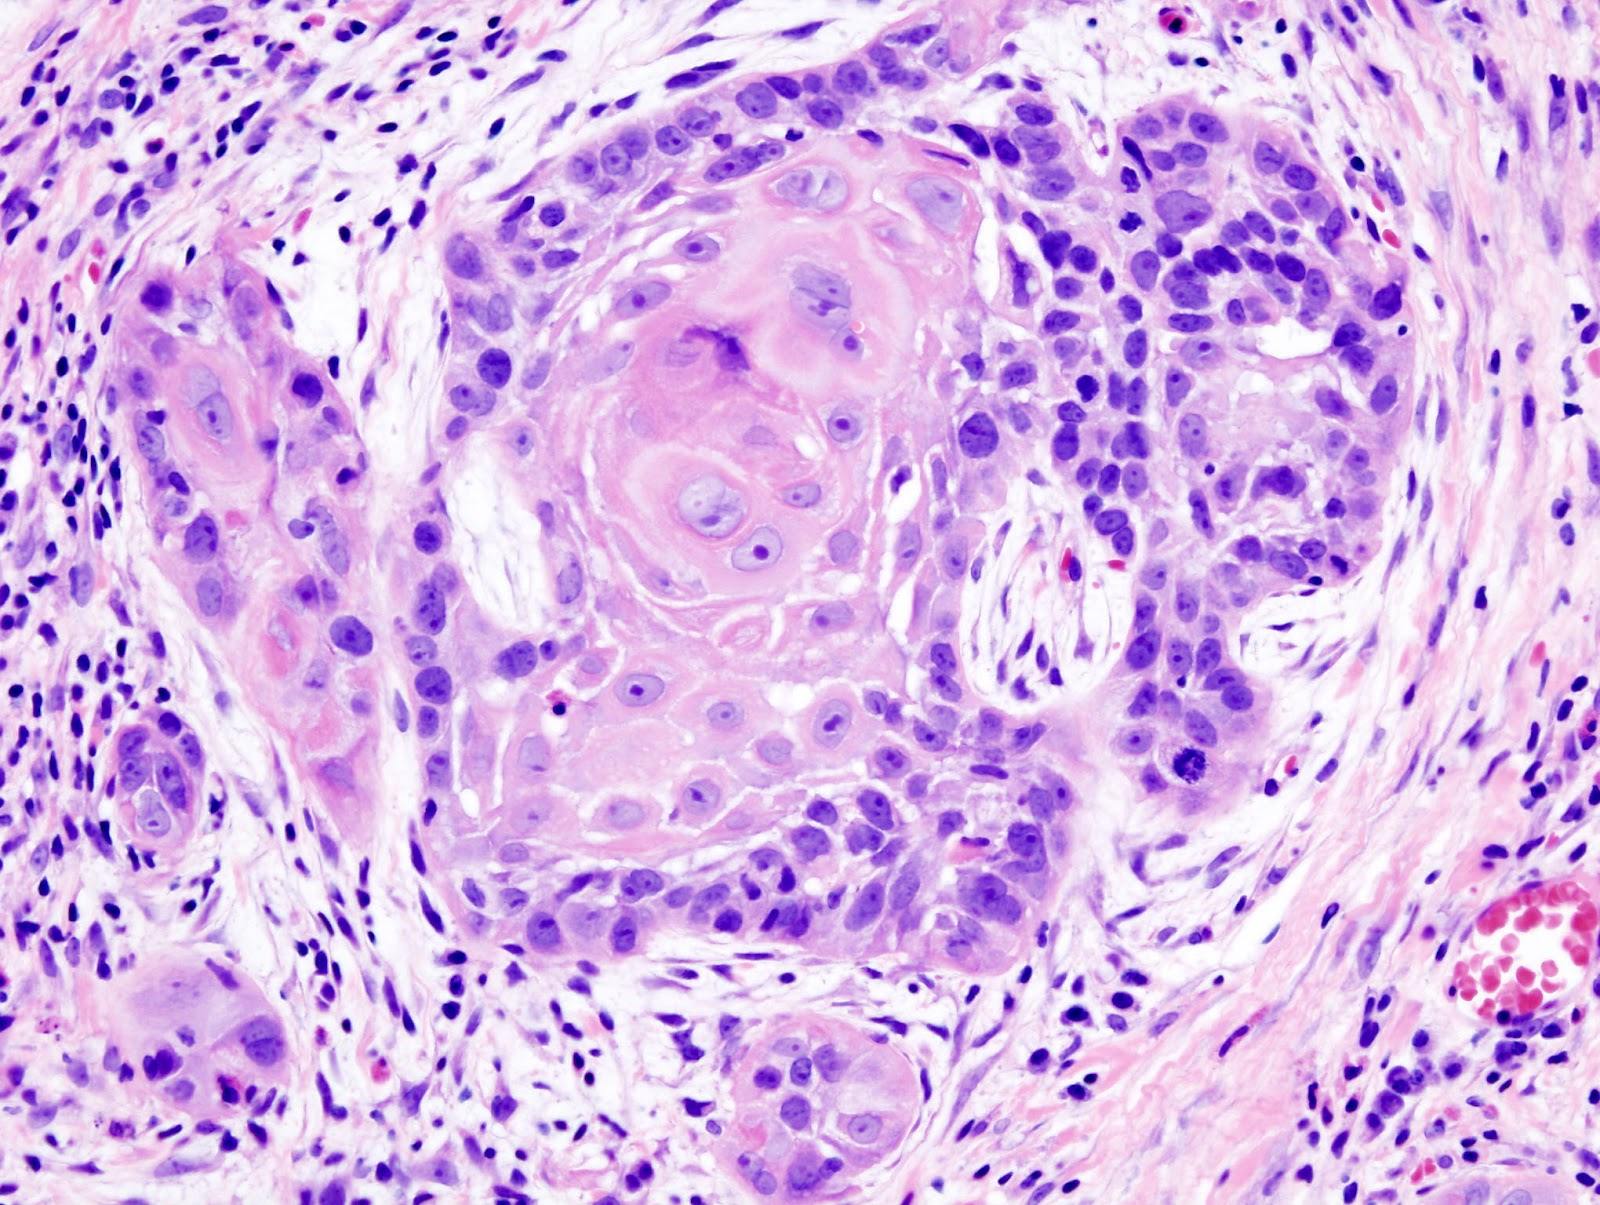

Click vào ảnh để xem 4 hình ảnh minh họa

Điều trị Squamous Cell Carcinoma hay Ung thư biểu mô tế bào vảy cụ thể phụ thuộc vào mức độ của bệnh, có thể bao gồm: Phẫu thuật, hóa trị hoặc xạ trị.